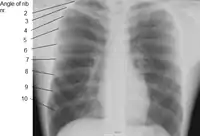

| Rib | |

![]() Detail of a single human rib | |